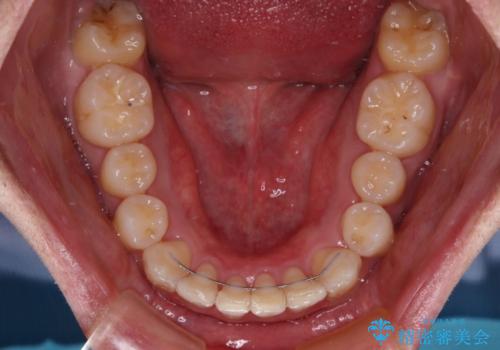

- 八重歯を気にして来院された患者様です。

顕著な上顎の八重歯とディープバイトであったため、上顎の左右第一小臼歯を抜歯することとしました。

犬歯歯根の位置や奥歯の咬み合わせから、ワイヤー装置での治療を強くおすすめいたしましたが、ご本人の強い希望により、妥協的な仕上がりとなることを了解いただき、インビザラインにて矯正治療を行うこととしました。

インビザライン単体で、左右ともに移動の難しい位置に歯根のある犬歯を整えるのは困難と判断し、補助装置を併用することとしました。

ディープバイトや奥歯の咬み合わせなど、インビザライン矯正では限界がありワイヤー装置での治療に及ばない仕上がりとなりました。

ただし、患者様としては八重歯や、それに伴う唇の閉じにくさが改善されたとのことで、納得いく状態での治療終了となりました。